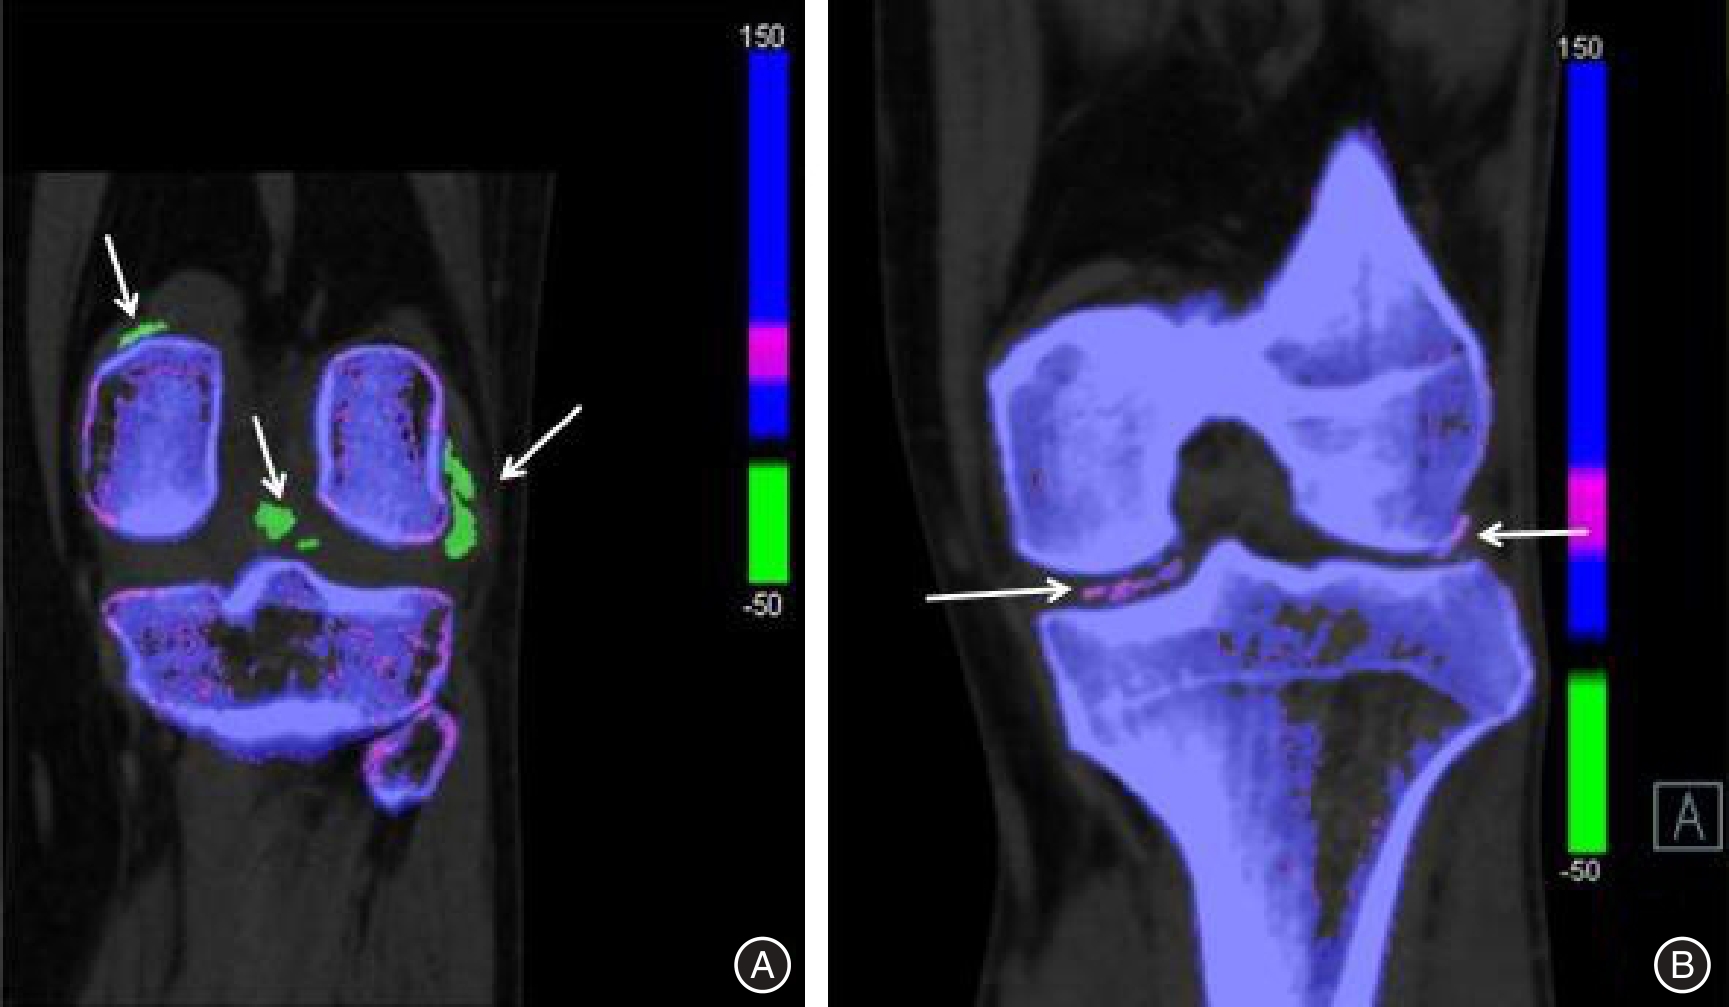

目的 探究双能量CT联合肌骨超声鉴别诊断焦磷酸钙沉积病与痛风性关节炎的价值。 方法 回顾性分析痛风性关节炎102例和焦磷酸钙沉积病102例患者的病历资料,分别记为痛风组和钙沉积组。所有患者均行双能量CT和肌骨超声检查,并以关节滑液或关节腔内晶体物质的穿刺结果作为金标准。评估双能量CT、肌骨超声诊断焦磷酸钙沉积病与痛风性关节炎的效能。 结果 痛风组患者的男性比例、血尿酸均高于钙沉积组(P < 0.05)。痛风组患者中膝关节、第一跖趾关节、踝关节的受累率偏高,钙沉积组患者中膝关节、腕关节、肩关节的受累率偏高。痛风组患者的骨皮质不规则、软骨损伤、半月板退行性变的所占比例均低于钙沉积组(P < 0.05)。痛风组患者的双轨征、痛风石、韧带内强回声、肌腱内强回声、骨侵蚀占比高于钙沉积组(P < 0.05),软骨钙化低于钙沉积组(P < 0.05)。双能量CT、肌骨超声及二者联合诊断焦磷酸钙沉积病和痛风性关节炎的灵敏度分别为86.27%、83.33%、94.12%,特异度分别为89.22%、88.24%、86.27%,阳性预测值分别为88.89%、87.63%、87.27%,阴性预测值分别为86.67%、84.11%、93.63%,准确率分别为87.75%、85.78%、90.20%,一致性Kappa值分别为0.755、0.716、0.804。 结论 双能量CT联合肌骨超声在焦磷酸钙沉积病与痛风性关节炎中的诊断效能良好,可用于辅助鉴别诊断两种疾病。

Objective To investigate the utility of dual?energy CT combined with musculoskeletal ultrasonography in differentiating between calcium pyrophosphate deposition disease and gouty arthritis. Methods A retrospective analysis was conducted on the medical records of 102 patients diagnosed with gouty arthritis and 102 patients diagnosed with calcium pyrophosphate deposition disease. These patients were categorized into the Gout group and Calcium Deposition group, respectively, based on their respective diagnoses. All patients underwent dual?energy CT and musculoskeletal ultrasonography examinations, while joint fluid aspiration results or intra?articular crystal material served as the gold standard for diagnosis. The diagnostic efficacy of dual?energy CT and musculoskeletal ultrasonography in discriminating between calcium pyrophosphate deposition disease and gouty arthritis was evaluated. Results In the gout group, the proportion of male patients and serum uric acid levels were significantly higher compared to those in the calcium deposition group (P < 0.05). The prevalence rates of knee joint, first metatarsophalangeal joint, and ankle joint involvement were higher in the gout group, while knee joint, wrist joint, and shoulder joint involvement rates were higher in the calcium deposition group. The proportions of irregular bone cortex, cartilage injury, and degenerative meniscus changes were lower in the gout group compared to the calcium deposition group (P < 0.05). The proportions of double contour sign, tophus formation, hyperechoic band within ligaments or tendons, and bone erosion were higher in the gout group compared to the calcium deposition group (P < 0.05), whereas cartilage calcification was lower in the gout group (P < 0.05). The sensitivities for diagnosing calcium pyrophosphate deposition disease and gouty arthritis using dual?energy CT scan alone, musculoskeletal ultrasound alone, and their combined use were 86.27%, 83.33%, and 94.12% respectively. The specificities for diagnosing these conditions using dual?energy CT scan alone,musculoskeletal ultrasound alone,and their combined use were 89.22%,88.24%, and 86.27% respectively. The positive predictive values were 88.89%, 87.63%, and 87.27%, respectively. The negative predictive values were 86.67%, 84.11%, and 93.63%, respectively. The accuracies were 87.75%, 85.78%, and 90.20% respectively. The agreement Kappa values were 0.755, 0.716, and 0.804 respectively. Conclusions The integration of dual?energy CT and musculoskeletal ultrasonography exhibits promising diagnostic efficacy in discriminating between calcium pyrophosphate deposition disease and gouty arthritis. This combined approach serves as a valuable adjunctive tool for the diagnosis of both conditions.